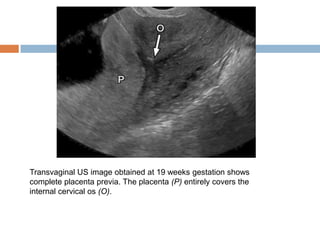

Placenta Previa

   Placenta previa refers to abnormal

implantation of the placenta in the lower

uterine segment, overlying or near the internal

cervical os

   Normally, the lower placental edge should be

at least 2 cm from the margin of the internal

cervical os.

   The diagnosis of placenta previa should not be

made before 15 weeks gestation.

Transvaginal US image obtained at 19 weeks gestation shows

complete placenta previa. The placenta (P) entirely covers the

internal cervical os (O).

Placenta Previa  Placenta previa refers to abnormal implantation of the placenta in the lower uterine segment, overlying or near the internal cervical os  Normally, the lower placental edge should be at least 2 cm from the margin of the internal cervical os.  The diagnosis of placenta previa should not be made before 15 weeks gestation.

Transvaginal US imageobtained at 19 weeks gestation shows complete placenta previa. The placenta (P) entirely covers the internal cervical os (O).